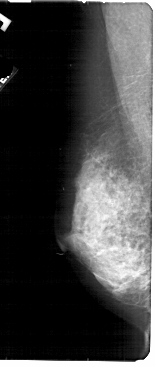

A_1875_1.LEFT_MLO

LEFT_MLO LINES 5491 PIXELS_PER_LINE 2311 BITS_PER_PIXEL 12 RESOLUTION 43.5 NON_OVERLAY